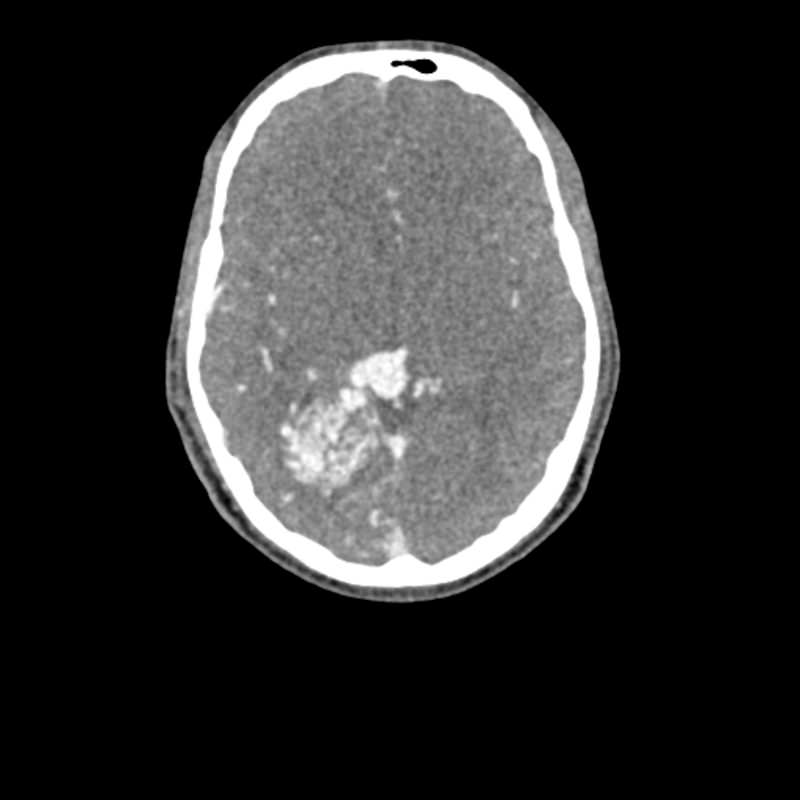

Dieses Phantom ist aus echten Patientendaten erstellt und wird mit neuester Technologie hergestellt. Knochen, Gefäße und Weichteilgewebe werden authentisch dargestellt mit realistischen CT-Werten für alle Gewebe bei 120 kVp Röhrenspannung in der CT. Wenn das Phantom vorwiegend bei anderen Röhrenspannungen (z. B. 100 kVp) eingesetzt werden soll, kann die Kalibrierung der CTWerte auf Wunsch entsprechend angepasst werden. Das Phantom liefert realistische Gewebekontraste in der Röntgen-Bildgebung. Lufträume sind durch ein Material mit etwa -80 Hounsfieldeinheiten aufgefüllt.

Das Kopf - Phantom liefert eine äußerst realistische Simulation einer Kopf- und Hals-CT-Angiographie (mit arterieller Kontrastierung) eines Patienten mit einer arteriovenösen Malformation auf der rechten Seite. Das Phantom wird in originalgetreuem Maßstab geliefert und beinhaltet die Halswirbelsäule bis zur Grundplatte des fünften Halswirbels.